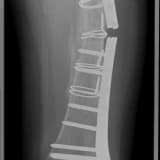

REVİZYON PROTEZ AMELİYATI

Kırıklar (Periprostetik Kırıklar):

Protez çevresindeki kemikte kırık

Travma veya düşme sonucu